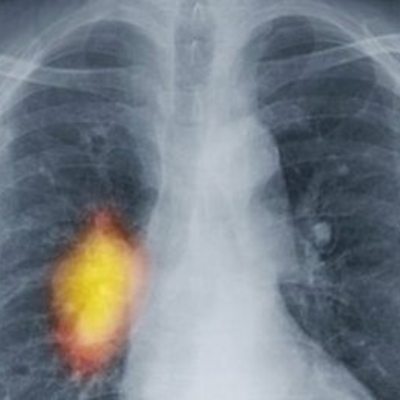

Today's Tom Feilden and Peter Johnson of Cancer Research discuss the Institute of Cancer Research's new centre.